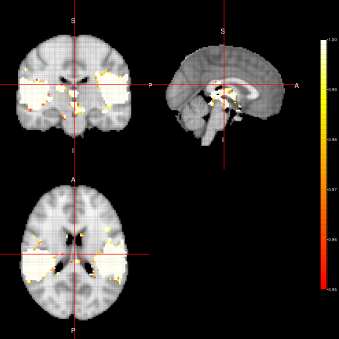

Figure 5: Activation Maps obtained for the ”voice localizer” example when using the AG-algorithm

In figure 5, we can see group activation maps obtained when using the AG-algorithm for every sampler option (FEST, FFBS, FSTS) at the individual level. From this example, we can conclude that with the AG-algorithm it is also possible to identify brain activation when analysing fMRI data for group activation.